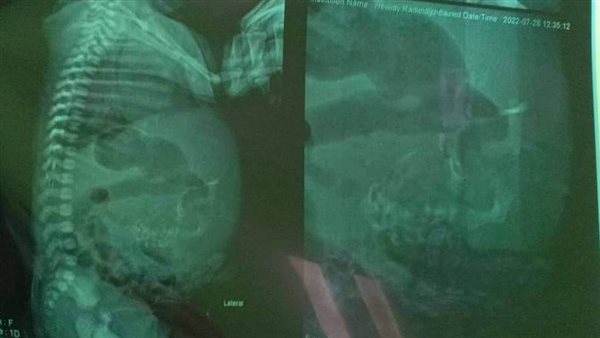

وأكد الدكتور أشرف الشرقاوي، مدير مستشفى الأطفال الجامعي بالمنصورة، أنه تم استقبال الطفلة أمس، وعمل أشعة رنين مغناطيسي وفحصها جيدا، وتحديد مكان الجنين داخلها، وجار تجهيز الحالة للجراحة لإزالته كاملًا.

وأجرت الأسرة أشعة تشخصية كشفت وجود جنين داخل بطن الطفلة، ولا يزال في بداية التكوين، وبعد قيام الطبيب بتشخيص الحالة، تم تحويلها إلى جراحة الأطفال بمستشفى طب الأطفال بجامعة المنصورة، لاتخاذ القرار الطبي المناسب.